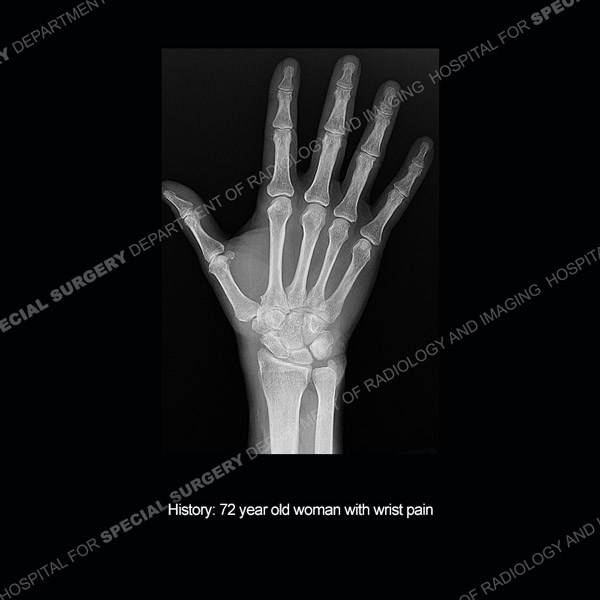

![]() |

Featured Ultrasound of the Month CaseCase 185: 55-year-old woman with right foot pain from naviculocuneiform joint osteoarthritis. |